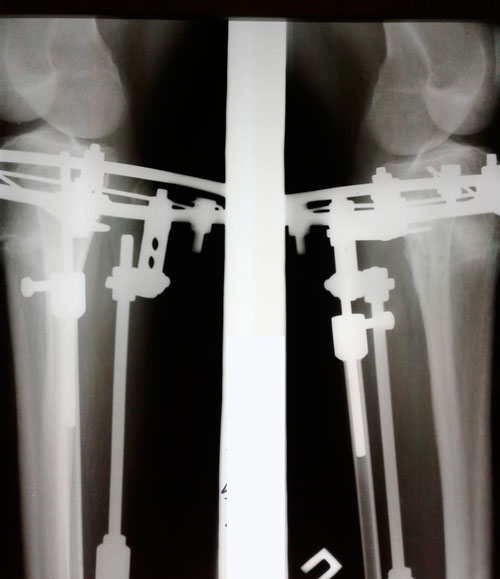

Исходник - 29 лет. Актобе.

Дата операции 15.05.2018г.

Двойная ротация, преимущественно справа.

Дата снятия аппаратов 01.08.2018г.

Срок сращения 75 дней.